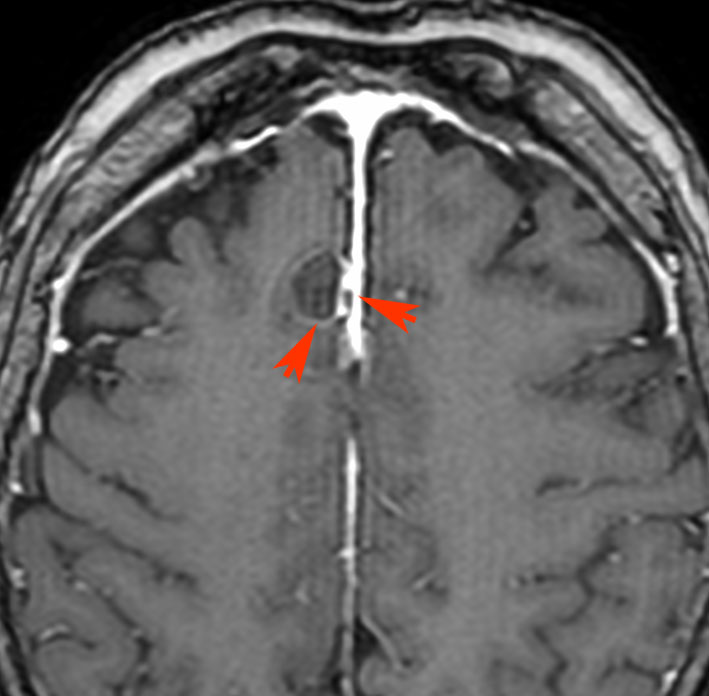

7歳の子が視力障害で発症しました。両耳側半盲という症状です。典型的な鞍隔膜下頭蓋咽頭腫です。ガドリニウム造影剤を入れないMRIでみえる,黄色い矢印の先の白い高信号は抗利尿ホルモンです。ですから下垂体機能もまだ残っていて,尿崩症はありません。視力障害が戻らないことがあるのでなるべく早く,経鼻的な手術で摘出した方がいいものです,簡単 o(^-^)o